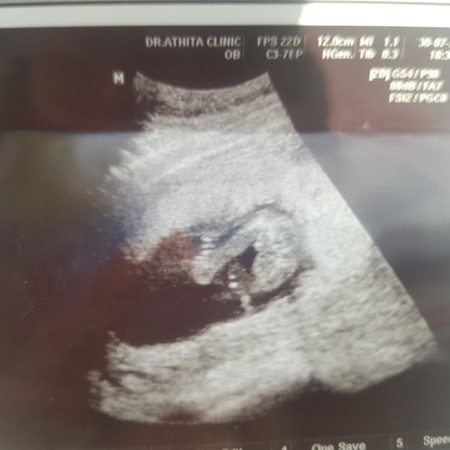

แม่ๆช่วยดูหน่อยค่ะ น้องเพศอะไร คุณหมอไม่ฟันธง

ช่วยดูเพศน้องหน่อยค่ะ

ดูยากเหมือนกันนะคะคุณแม่ บ้านนี้ซาวด์ตอน 12วีค5วัน หมอบอก70%ผช.ค่ะ มีติ่งน้อยๆโผล่มาแบบในภาพนี้ ตอนนี้20วีคแล้ว ผช.ชัวร์เลยค่ะ